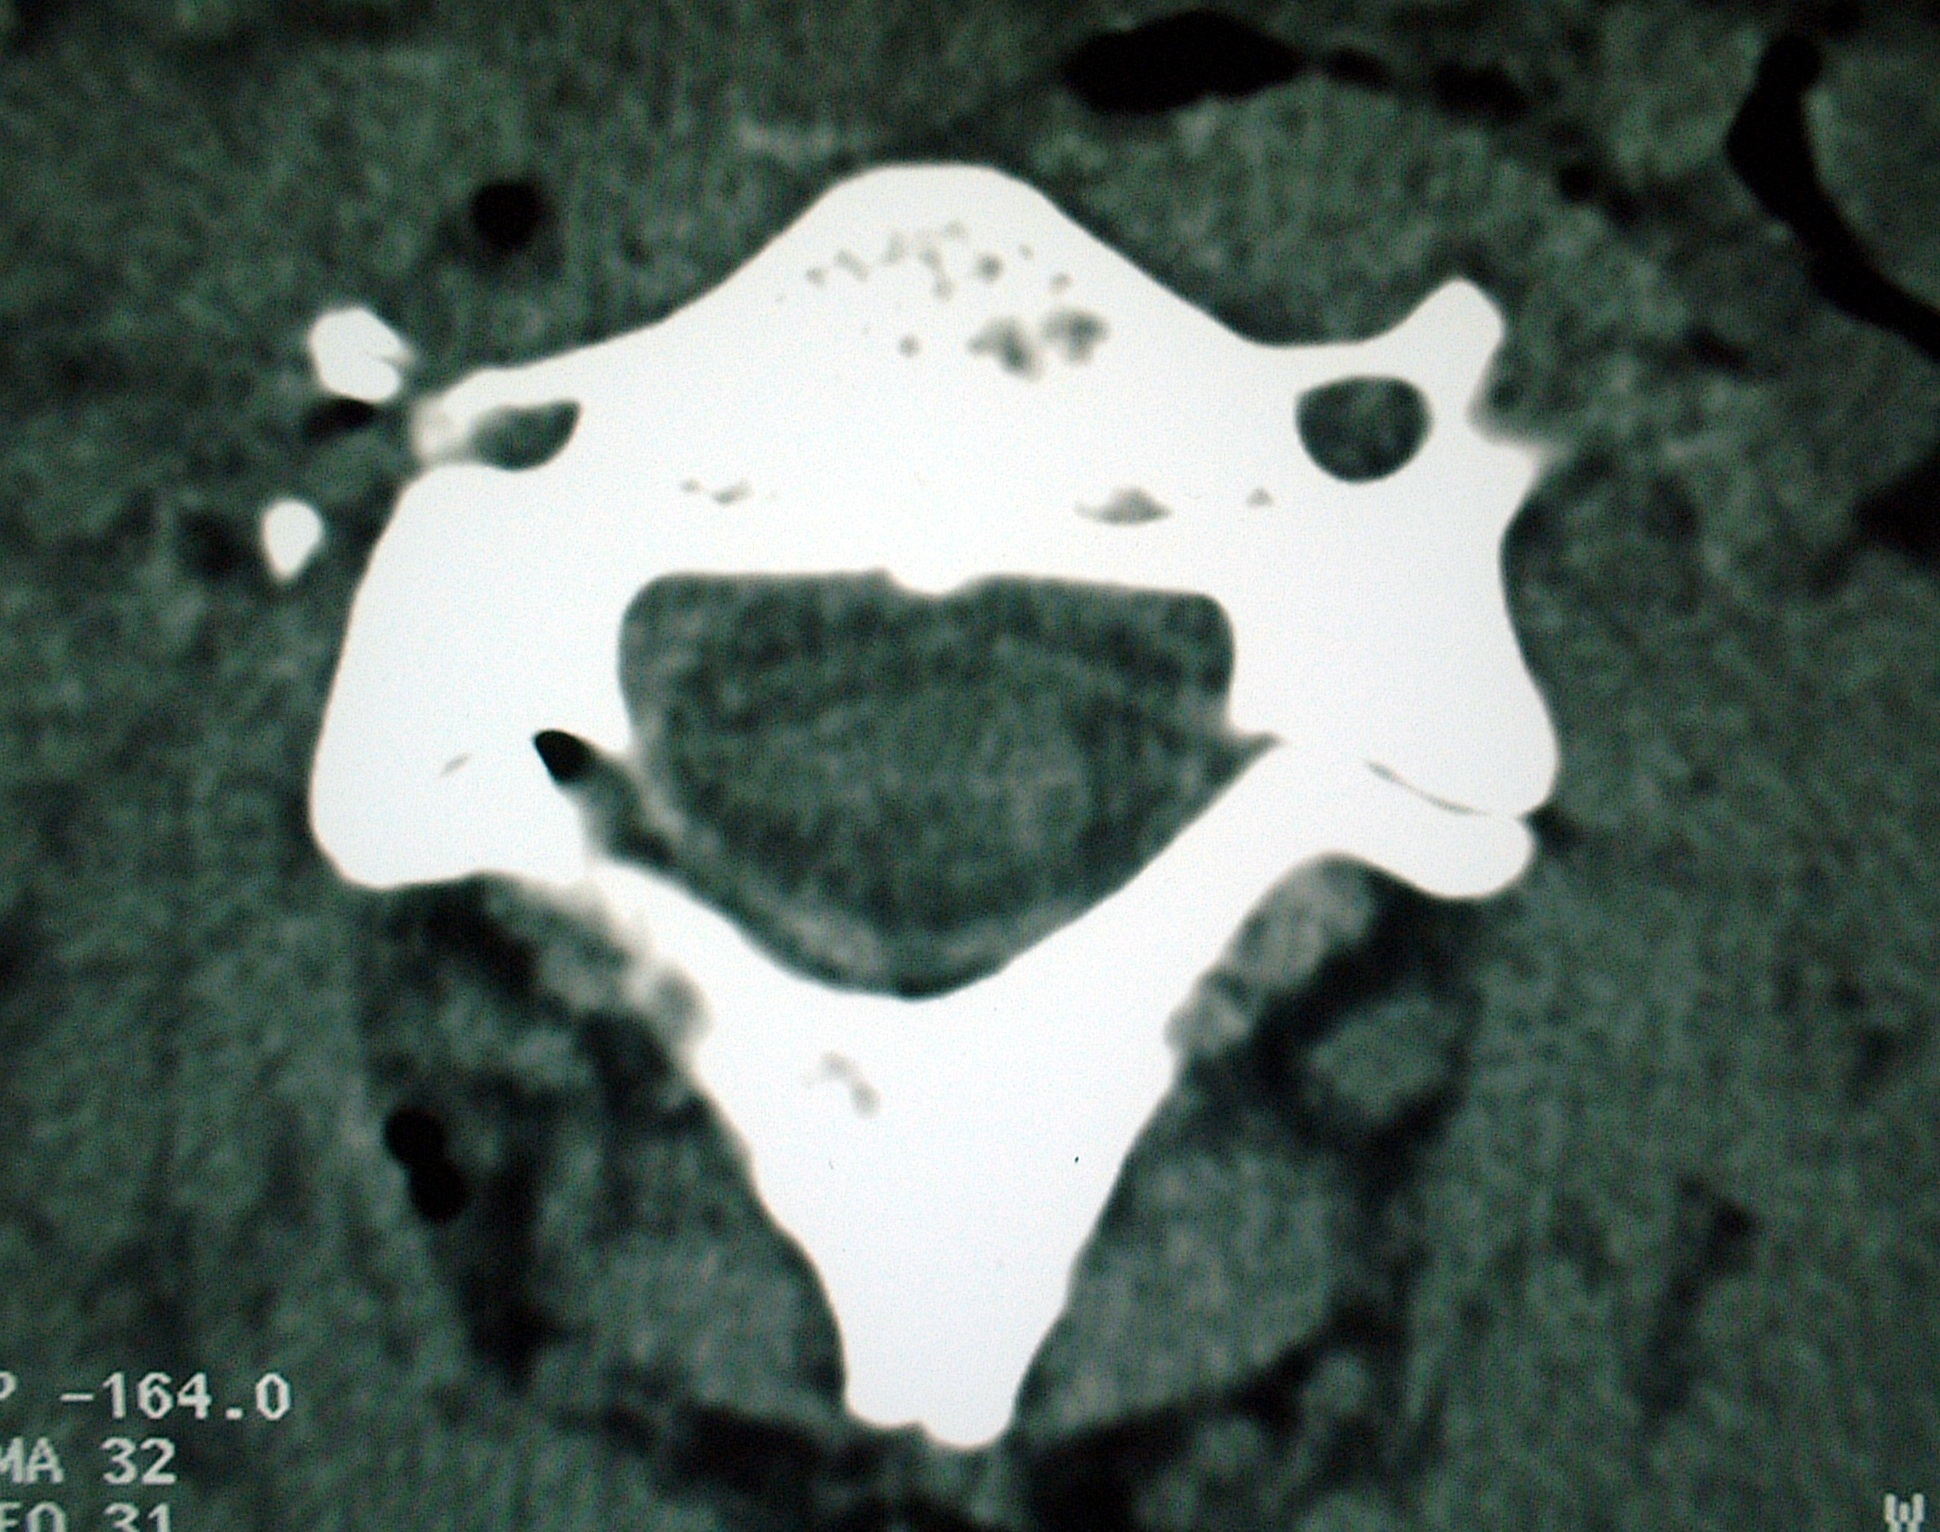

Open fracture of a cervical transverse process as a result of a bull-horn wound

Se presenta el caso de un paciente que sufrió una herida por asta de toro en la region cervical, que causó una fractura de la apófisis transversa del lado dcho de la 4ª vertebra cervical. No se ha encontrado en la literatura ninguna fractura abierta producida por asta de toro. El tratamiento consistió como es mandatorio en la exploración minuciosa de la herida, limpieza y colocación de drenajes. En la intervención, realizada de forma urgente, se comprobó una perfecta cervicotomía con un abordaje similar al realizado quirúrgicamente para la cirugía de la columna cervical. La exploración posterior mediante CT-Scan y RMN demostró una lesion de la apófisis transversa de C4, sin afectación de la arteria vertebral. Este caso alerta ante las posibles variaciones lesionales y de complicaciones de las heridas producidas por asta de toro, insistiendo en la necesidad de que estas lesiones sean tratadas por personal especialmente entrenado.Descargas